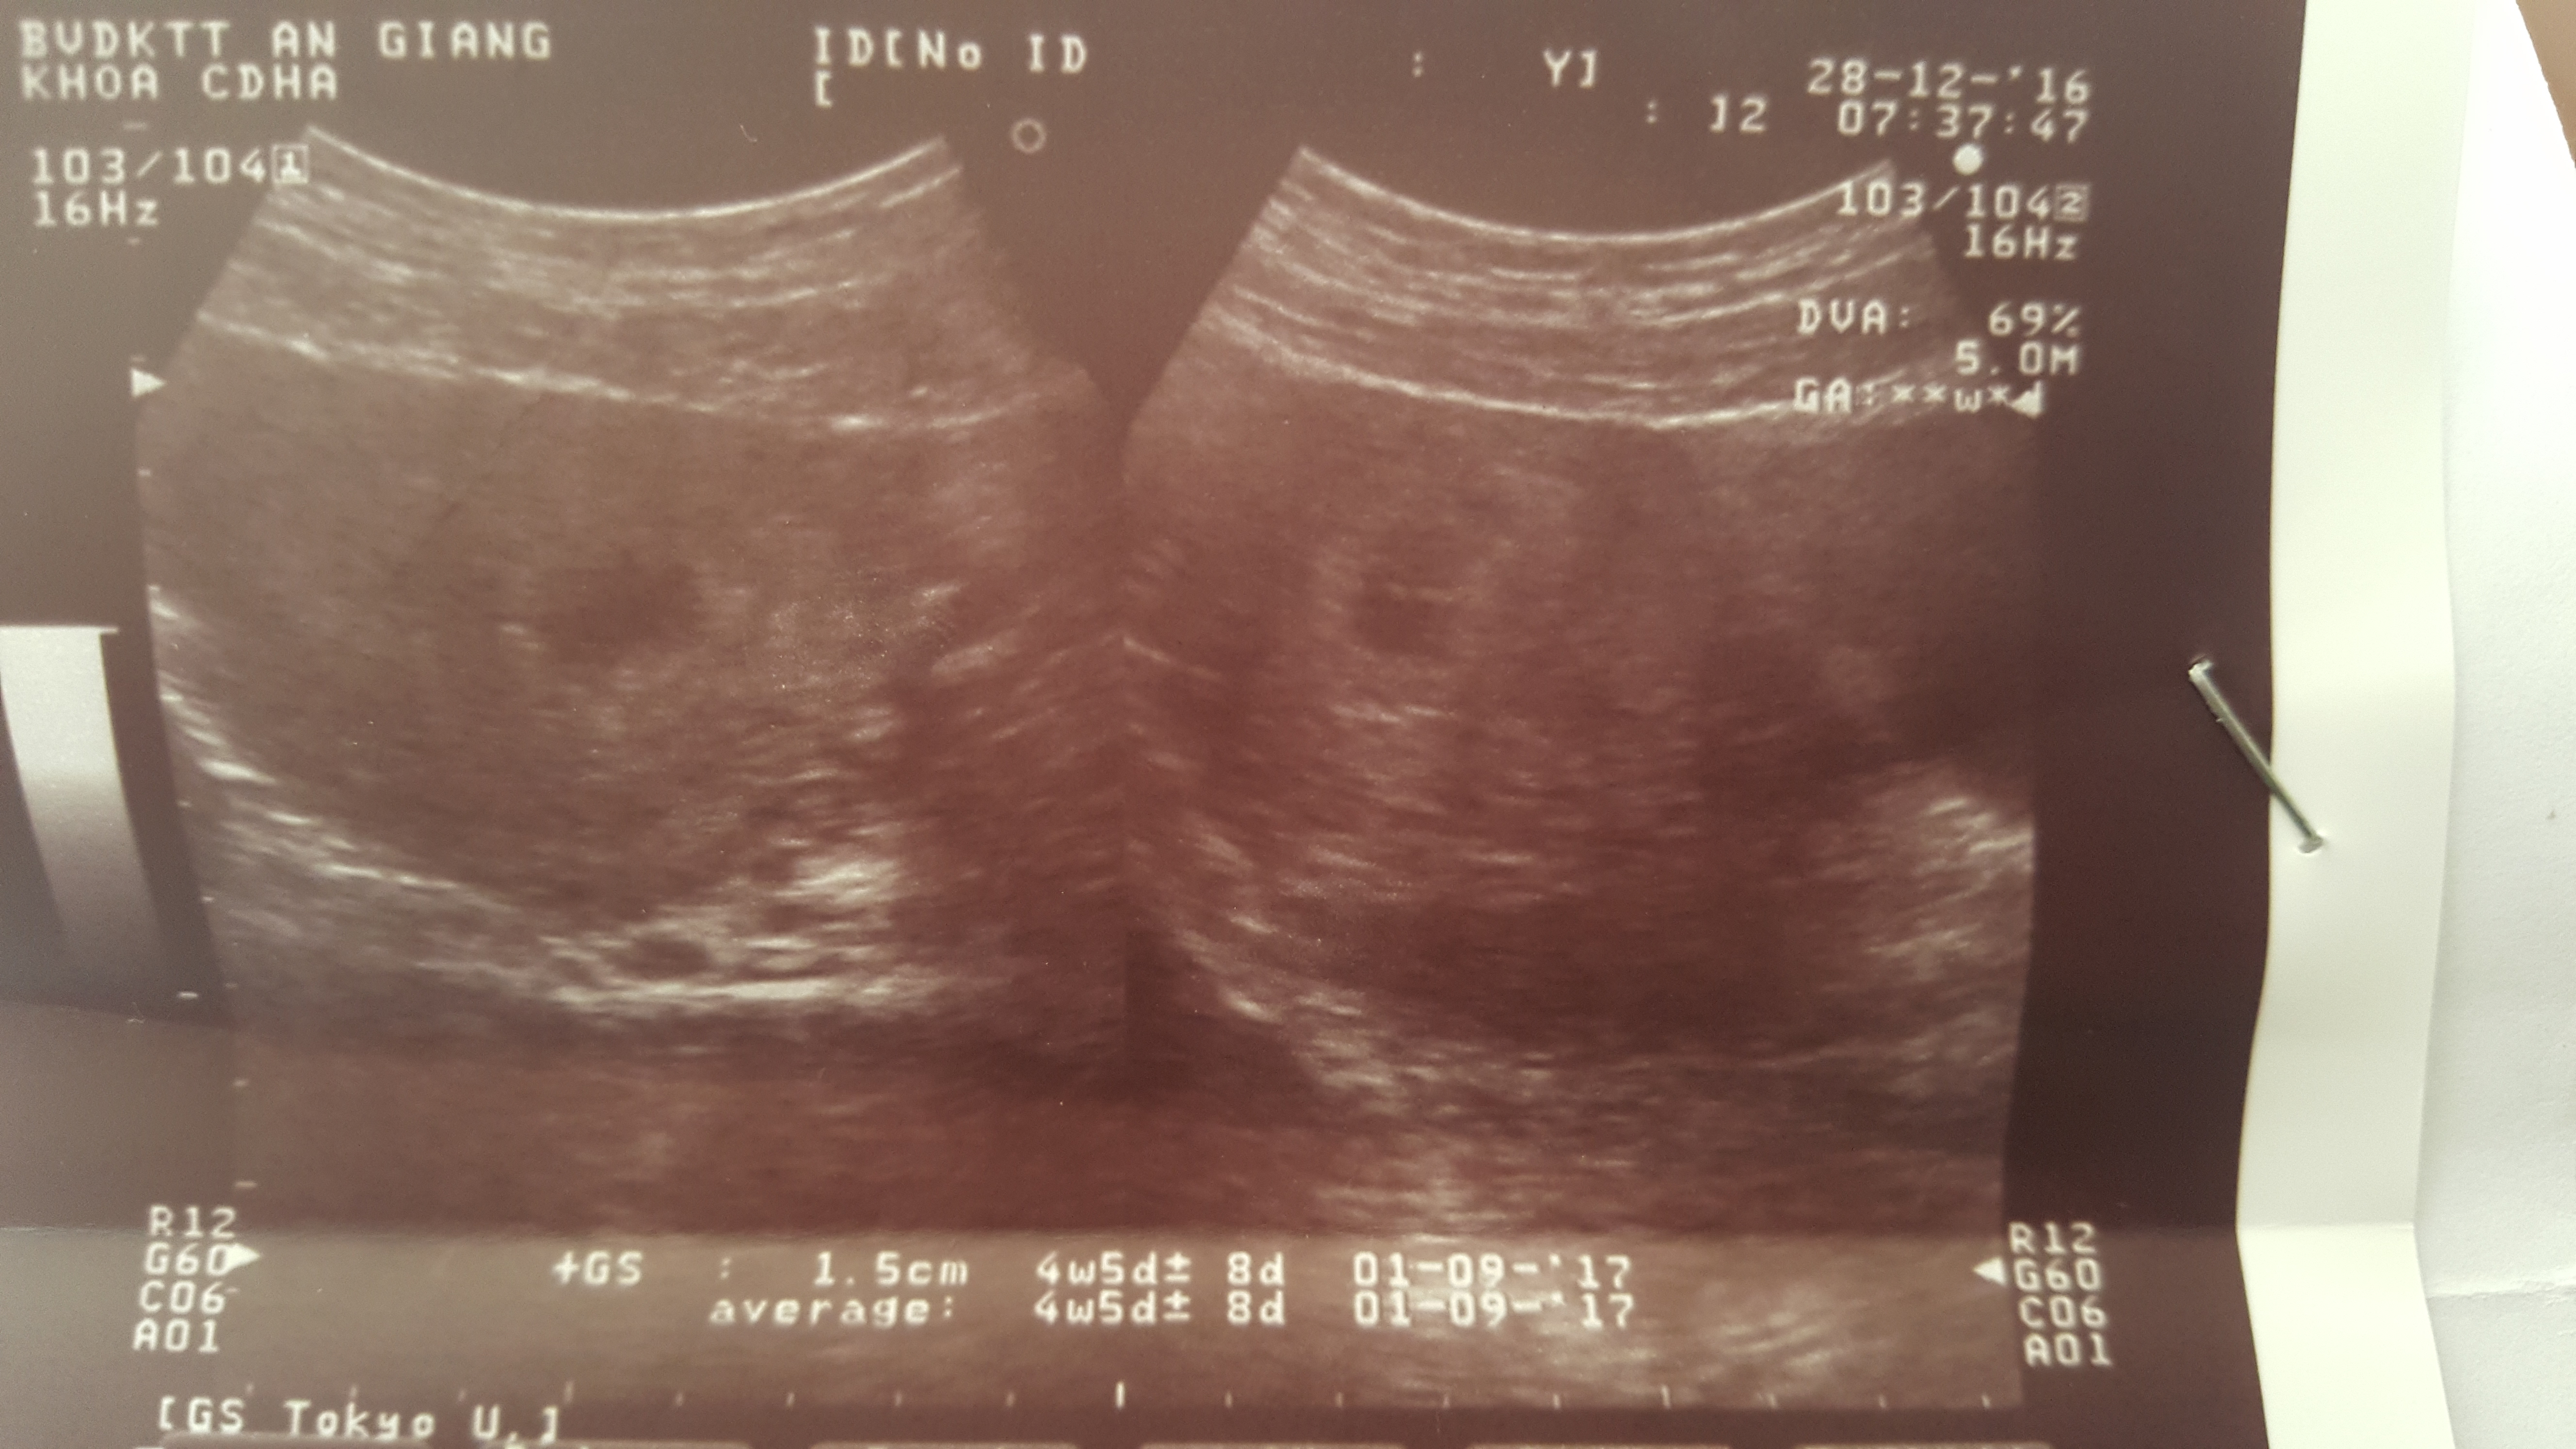

Vợ chồng em có khám hiếm muộn trên BV Từ Dũ, điều trị đến giai đoạn canh ngày rụng trứng thì giao hợp với thuốc hỗ trợ bác sĩ cho. Kết quả là vợ em dính bầu, trong khoảng thời gian này vợ em đau râm rang ở bụng dưới nên đi siêu âm ở PK tư thì bs nói " Trong lòng tử cung có 1 túi thai, bên trong có yolksac, chưa có phôi thai - Gs 12 mm tụt thấp - Kết Luận 1 thai sống trong lòng TC 5 tuần 2 ngày, dọa sẩy". Lo lắng quá, ngày hôm sau tụi em vào bệnh viện đa khoa tỉnh An Giang khám thì siêu âm lại, hình em đính kèm bên dưới, ra kết quả thai bình thường. Bác sĩ cho e hỏi nhìn hình siêu âm đó có phãi bình thường không ạ? BD cho vợ em uống viên sắt, 1 ngày 1 viên, 3 tuần sau tái khám. Nay em nhờ bác sĩ xem giúp em hình siêu âm như vậy có đúng là bình thường không ạ, cho em xin lời khuyên đễ dưỡng thai cho vợ em. Chân thành cảm ơn bác sĩ.

Nên khám lại sau 2 tuần và siêu âm xem thai nhi phát triển ra sao. Đa số các trường hợp thai phát triển bình thường mà.